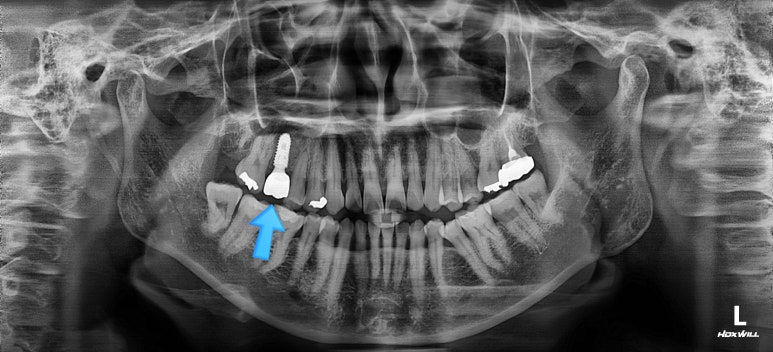

초진 때의 사진입니다.

제일 하단의 X-ray에서 문제점이 보이는데요.

해당 부분의 어금니 1개가 없었어요.

어금니가 없어진지 꽤 시간이 흘렀기 때문에 몇 가지 문제점이 나타나는데요.

치아가 없는 자리에 바로 임플란트가 불가능합니다.

치아를 뽑자마자 임플란트를 했다면, 치료는 간단했겠지만 이번의 경우는 시간이 오래 지나서 뒤쪽 어금니가 발치된 자리로 쓰러졌어요.

앞쪽 치열들도 발치된 자리로 조금씩 이동하는 바람에 틈새가 듬성듬성 생겼어요.

경우에 따라서는 맞물리는 치아(이번 환자분의 경우 아랫니)가 솟구쳐 오르면서 어금니 교합이 망가져요.